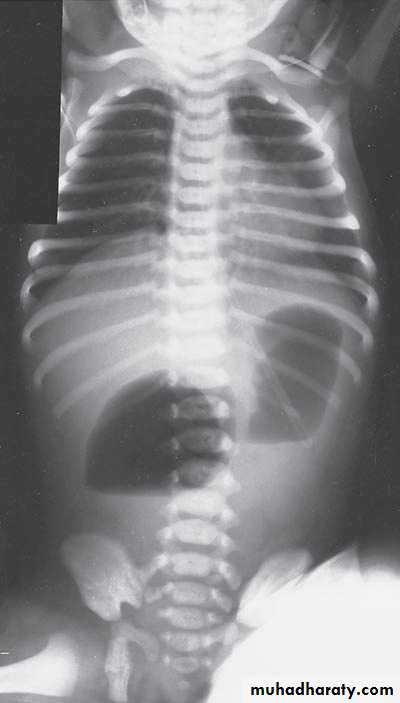

Respiratory Distress in the Newborn

Scaphoid abdomen